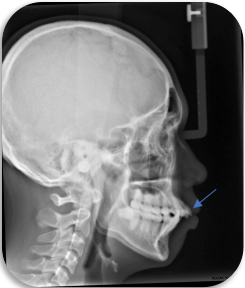

治疗前

拔牙治疗后

鼻唇角:鼻唇角越小,面型越突

当前牙后移,上唇随之后移,鼻唇角增大,突面型改善